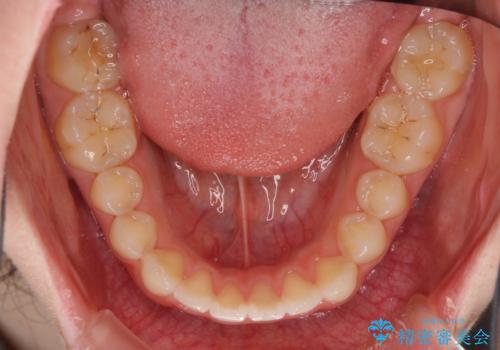

上下前歯の歯列不正はインビザラインにより歯列を整え、その後に、前歯5本をオールセラミッククラウンにて補綴治療することとしました。

矯正治療にて歯並びを整えた後に、虫歯の大きかった5本の歯をセラミッククラウンにて補綴し、明るい口元になりました。